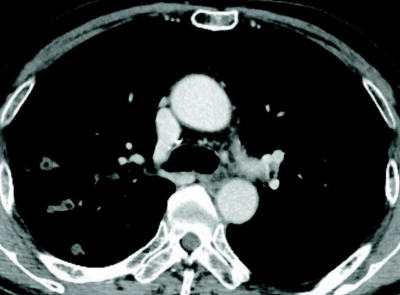

71 歳の男性。血痰を主訴に来院した。2か月前から微熱があり、2週前から断続的に血痰の排出が続いている。かかりつけ医で糖尿病の内服加療中であるが、コントロールは良くないと言われているという。呼吸音は両側胸部に coarse cracklesを聴取する。胸部エックス線写真及び胸部造影 CTを別に示す。

亜急性の経過、血痰、画像所見、糖尿病による易感染により肺結核の可能性を考える必要あり。